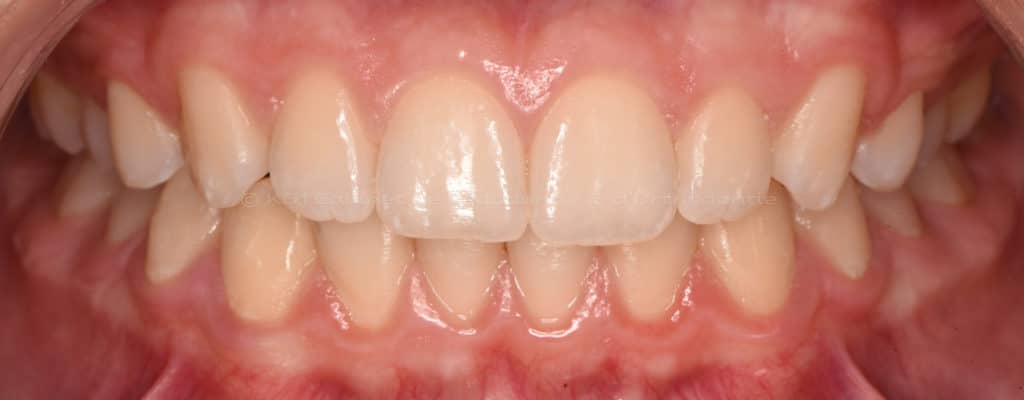

Cas #1 – Traitement avec des bagues, deuxièmes prémolaires et dent de sagesse supérieures ectopiques.